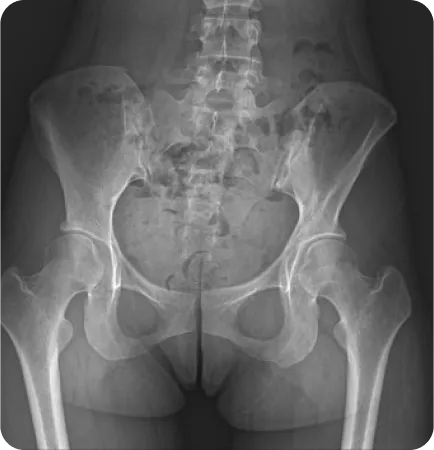

Before & After

해당 사진은 수정없는 실제 치료사진입니다.

환자의 치료결과는 환자의 상태, 치료방법 등에 따라 차이가 발생할 수 있습니다.